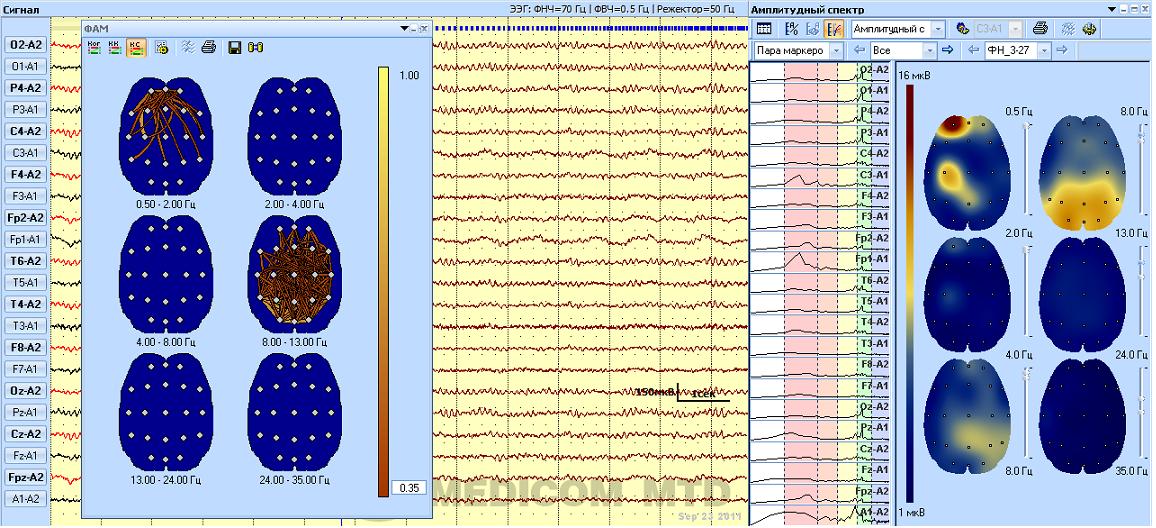

Э лектрическая активность мозга при решении логических задач (возраст 65 лет)

ЭЭГ изменения в функционирования мозга в большинстве случаев остаются скрытыми и неосознаваемыми , долго не проявляются какими - либо психическими отклонениями или поведенческими особенностями. Они выявляются неожиданно, довольно резко в те периоды жизни, когда к организму предъявляются повышенные требования. Это могут быть стрессовые состояния, интеллектуальные или эмоциональные перегрузки , соматические заболевания . Так же скрытно, без жалоб на ухудшение состояния здоровья протекают и начальные стадии ускоренного патологического старения мозга. В первую очередь это относится к болезни Альцгеймера и старческой деменции Альцгеймерского типа. Однако изменения ЭЭГ достаточно четко выявляют как самые ранние признаки нарушений функционирования мозга , которые опережают проявление этих изминений в поведенческих реакциях. По современным представлениям общее и локальное снижение мощности ритмов в динамике может свидетельствовать о снижении функциональной активности нейронов коры мозга, которая постепенно ведет к атрофии (дегенерации) мозгового вещества, что в свою очередь постепенно приводит к снижению умственных способностей и неуклонно нарастающей деме нции.